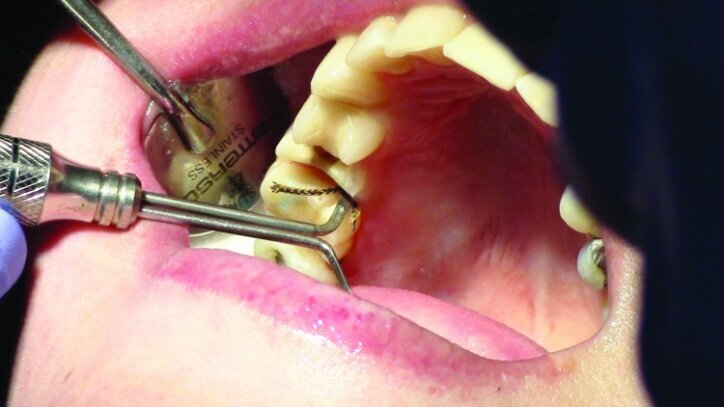

Tissue management was obtained with ViscoStat Clear, gingival haemostatic gel, 25 percent (m/m) aluminum chloride (Figs. 16 & 17). Gingival retraction was obtained using a two-cord system. First, a #00 size cord from Ultradent was placed on the mesial and distal of both preparations (Figs. 18 & 19).

Additional haemostatic gel was used prior to the second cord. The second cord was #2 size cord from Ultradent (Figs. 20 & 21a). A minimum of four minutes with both cords in place is needed for adequate retraction of the soft tissue (Fig. 21b).